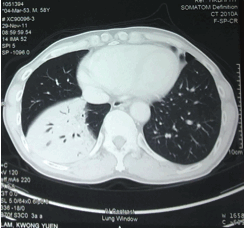

He was afebrile and had no chest symptoms. Blood tests including complete blood count, liver and renal functions were normal. His LDH level and Albumin/globulin level were normal. Sputum culture and AFB smear were negative. He was given Augmentin for one week empirically; and he performed private CT thorax with contrast in the same month.

The X-ray and CT features are non-specific, ranging from consolidation, lung mass to nodules; but interestingly, it seldom presents with pleural effusion. CT scan is useful in staging for detection of any enlargement of non-palpable lymph nodes. Pulmonary MALT lymphoma is not a typically FDG avid lymphoma; therefore PET scan would not add information to the diagnosis or staging of the disease.